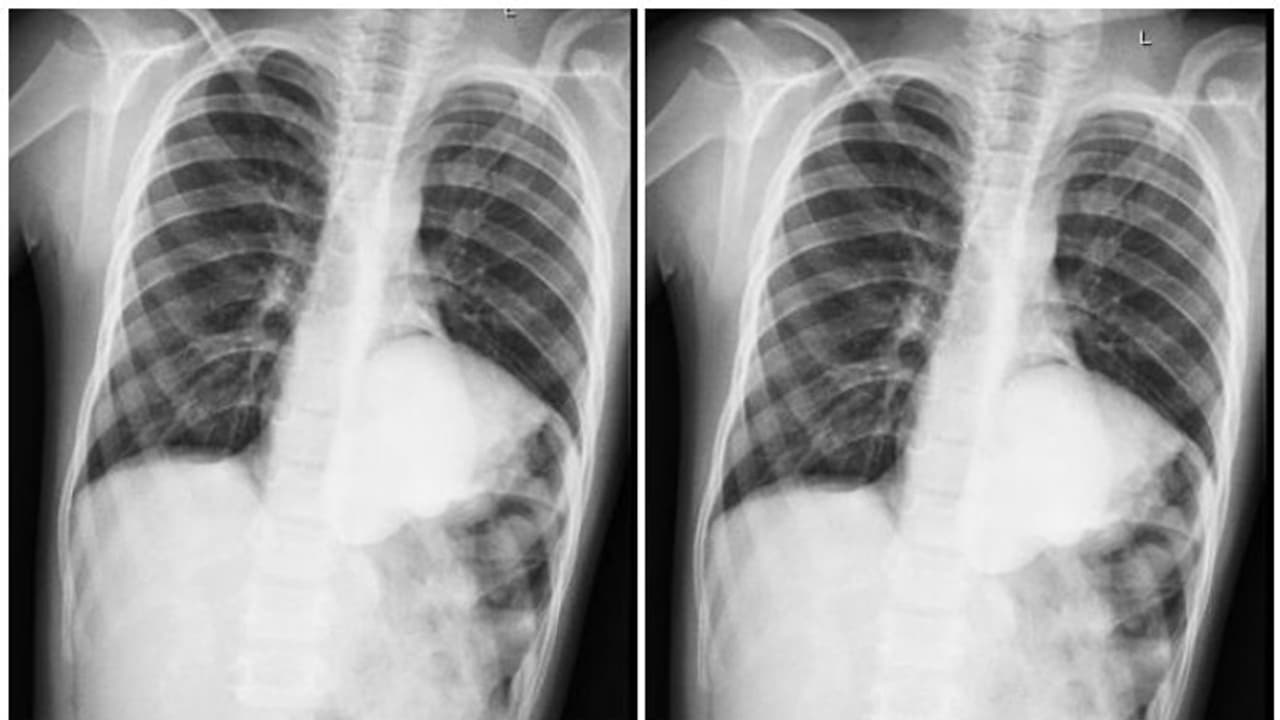

ജനിച്ച് ആറ് മാസം മുതൽ കുട്ടിക്ക് ഇടയ്ക്കിടെ ചുമയും പനിയും ഛർദ്ദിലും മറ്റ് അസ്വാസ്ഥ്യങ്ങളും അനുഭവപ്പെട്ടിരുന്നു. ഇതേതുടർന്ന് നടത്തിയ വിശദമായ പരിശോധനയിലാണ് ഇടത് വശത്തെ ഡയഫ്രമിൽ 6 സെന്റി മീറ്റർ വലുപ്പമുള്ള ഹെർണിയ കണ്ടെത്തുന്നത്. അതുവഴി ആന്തരിക അവയവങ്ങളായ കുടലും ഇടത് കിഡ്നിയും മുകളിലേക്ക് കയറി വരുകയും കിഡ്നിയിൽ ജന്മനാ ഉണ്ടായ തടസംമൂലം ഹൈഡ്രോ നെഫ്രോസിസ് ഉണ്ടാവുകയും ആയിരുന്നു.

(വൃക്കയെ മൂത്രാശയവുമായി ബന്ധിപ്പിക്കുന്ന ട്യൂബിലെ തടസ്സം മൂലമാണ് ഹൈഡ്രോനെഫ്രോസിസ് ഉണ്ടാകുന്നത്. ) അടുത്തകാലത്ത് വയറിന്റെ ഇടത് ഭാഗത്ത് കഠിനമായ വേദനയും ഇടയ്ക്കിടെ ഛർദ്ദിലും അനുഭവപ്പെട്ടിരുന്നു. കണക്കുകൾ അനുസരിച്ച് പതിനാറായിരത്തിൽ ഒരാൾക്ക് മാത്രമാണ് ജന്മനാ ഡയഫ്രമാറ്റിക് ഹെർണിയ ഉണ്ടാകുന്നത്. അതിൽ തന്നെ നെഞ്ചിനുള്ളിൽ വൃക്ക സ്ഥിതി ചെയ്യുന്ന കേസുകൾ 140 എണ്ണം മാത്രമേ റിപ്പോർട്ട് ചെയ്യപ്പെട്ടിട്ടുള്ളു.

ഡയഫ്രമാറ്റിക് ഹെർണിയയും തൊറാസിക് കിഡ്നി ഹൈഡ്രോ നെഫ്രോസിസും ഓപ്പൺ സർജറിയിലൂടെ പരിഹരിക്കപ്പെട്ട ഒരു കേസ് മുൻപ് റിപ്പോർട്ട് ചെയ്തിട്ടുണ്ട്. ഇത്തരമൊരു കേസിൽ ലാപ്രോസ്കോപിക് സർജറിയിലൂടെ മെഷ് വെച്ച് ഹെർണിയ റിപ്പയർ ചെയ്യുന്നതോടൊപ്പം പൈലോപ്ലാസ്റ്റിയിലൂടെ കിഡ്നി റിപ്പയർ ചെയ്യുന്നതും ഇതാദ്യമായാണ്.